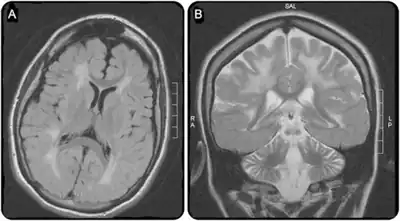

a)Extensive white matter disease b) atrophy of frontal hemispheres and cerebellum -

Cerebral CT-scan at 4 years old. Red arrows show brain calcifications (A) and diffuse white matter abnormalities (B). From Mafi et al., 2020[15]